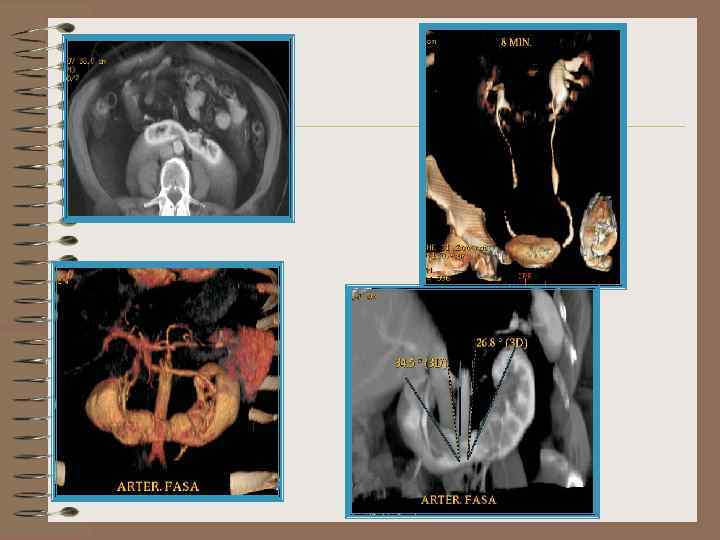

Подковообразная почка 1 минута

КТ – подковообразная почка Нативная Контрастирование выделительная фаза

КТ- подковообразная почка.

МРТ